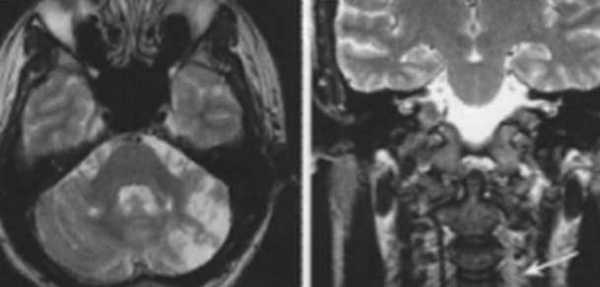

Ишемическое ОНМК, ствол мозга (подострый период)

Одно из преимуществ МРТ в оценке последствий инсульта - возможность визуализировать нисходящую Валлеровскую дегенерацию аксонов в стволе мозга и кортико-спинальном тракте на стороне поражения.

Ишемический инсульт в ВББ слева. Отсутствие феномена пустоты потока на уровне экстракраниального отдела левой позвоночной артерии (признаки замедления кровотока).